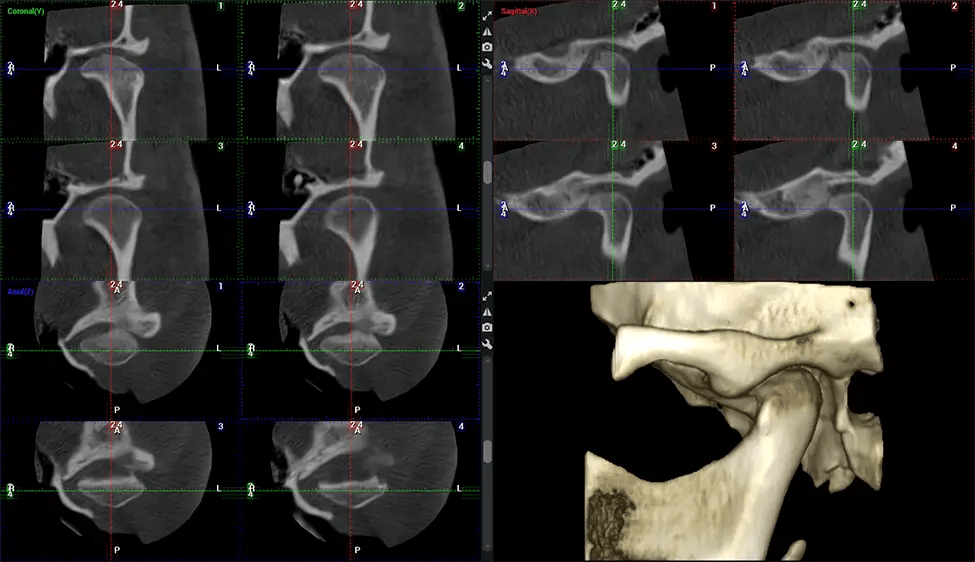

Full Skull to C7 of the Spine

Upper Cervical Chiropractor Diagnosing structural problems in the C1-C2 vertebrae, assessing misalignment and instability, and evaluating chronic pain. Enables precise, weight-bearing views of the upper cervical spine, helping to identify abnormalities that inform targeted, non-invasive therapies.

Planmeca Viso G7 CBCT ( Cone Beam CT Scan ) is designed to surpass the demands of industry leaders, specialists, and large institutions. It’s has a large ø25×30 cm sensor with four built-in cameras. It can capture unlimited volume sizes from a ø3×3 cm to a ø30x30cm volume capturing the skullcap through C7 on the cervical spine. The Planmeca Viso G7 offers the industry’s largest single volume scan of ø30×19 cm. It’s poised to handle advanced imaging modalities such as Planmeca ProFace® and Planmeca 4D™ Jaw Motion technology. The occipital head support allows an unimpeded view of facial tissue.